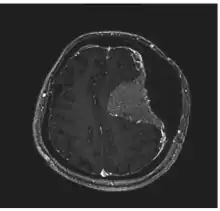

| A human skull showing hyperostosis | |

Image revealed a bilateral frontoparietal bone hyperostosis, particularly in the left side